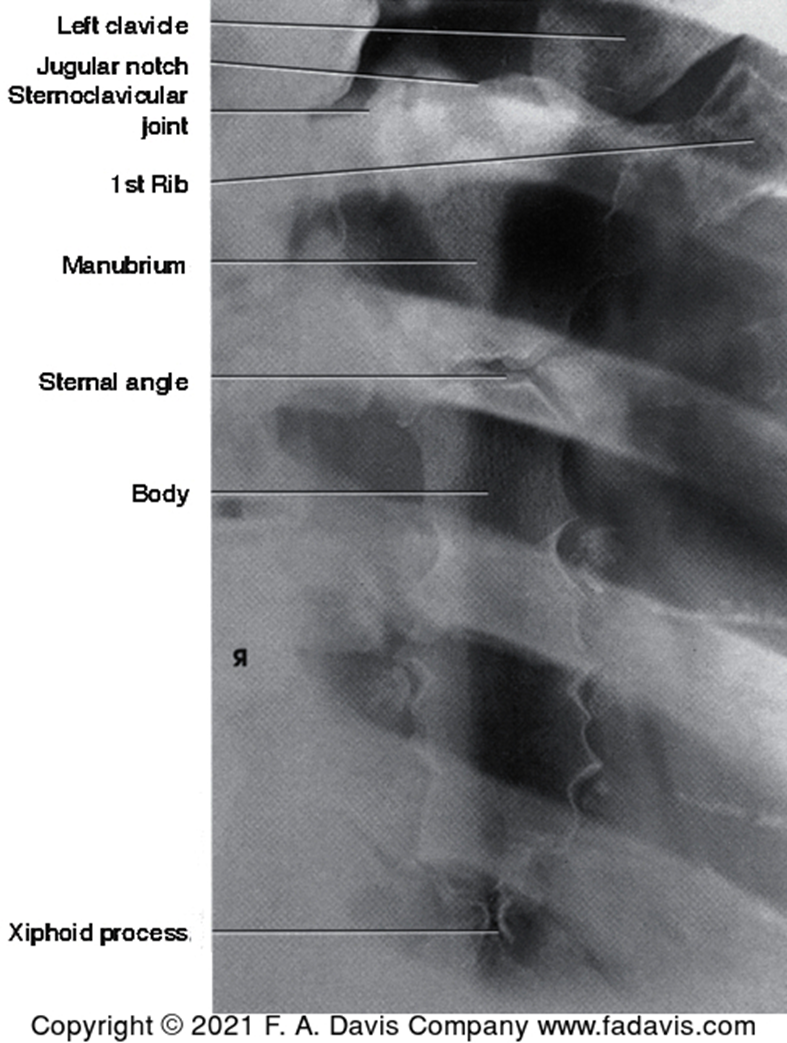

standard imaging for sternum

posterior oblique

lateral

Where is the CR for sternal imaging

through SC joint, body of sternum, or the clavicle

What view is this

sternal posterior oblique